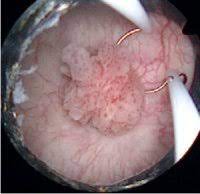

Η σημαντικότερη εξέταση είναι η κυστεοσκόπηση η οποία θα αναδείξει τη βλάβη, τη θέση της, το μέγεθος, τον αριθμό και τη σχέση της με σημαντικές ανατομικές δομές.  Η αξονική τομογραφία έχει  θέση στη διερεύνηση της  αιματουρίας όταν η νόσος εντοπίζεται κοντά στα ουρητηρικά στόμια αφού θα δώσει πληροφορίες για την εμπλοκή του ανώτερου ουροποιητικού .Στη διαγνωστική φαρέτρα μας, βρίσκεται επίσης η κυτταρολογική εξέταση ούρων, καθώς και ο υπερηχογραφικός έλεγχος που χρησιμοποιούνται τόσο στη διάγνωση όσο και στην παρακολούθηση μετά την αρχική θεραπεία.

Η αρχική αντιμετώπιση του όγκου της κύστης είναι η διουρηθρική εκτομή. Στόχος της επέμβασης είναι η εξαίρεση του όγκου σε υγιή όρια και ικανοποιητικό βάθος προκειμένου να σταδιοποιηθεί τοπικά η νόσος, πράγμα που αποτελεί το πιο σημαντικό αρχικό βήμα ώστε να διαχωρίσουμε τους όγκους σε επιφανειακούς, όπου  η διουρηθρική εκτομή είναι θεραπευτική, και σε διηθητικούς (διήθηση του μυικού χιτώνα) όπου η ενδεδειγμένη θεραπεία συνήθως είναι η ριζική κυστεκτομή.